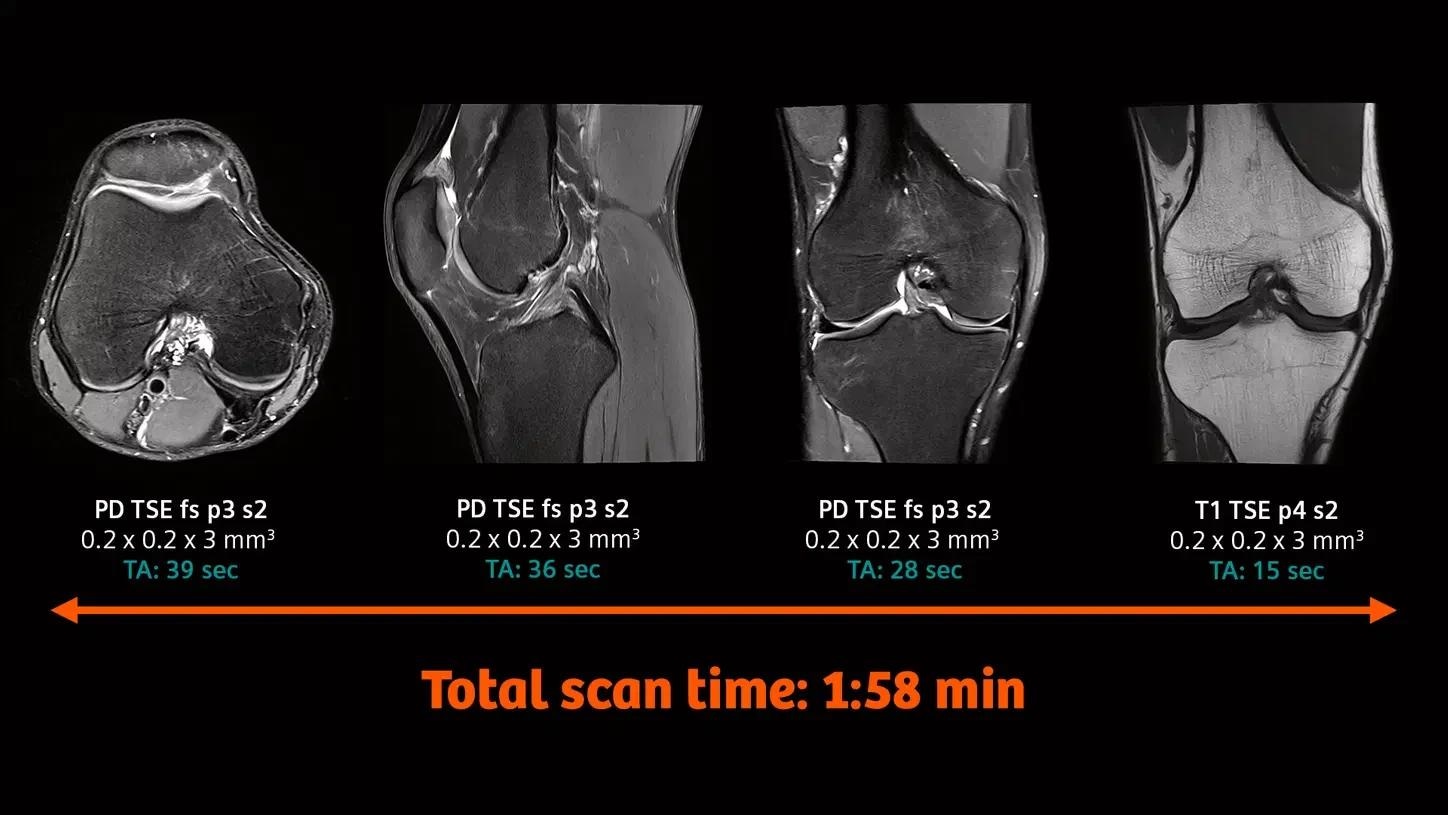

Knee imaging with the new Tx/Rx Knee 18

The new coil provides high-resolution knee imaging as well as a wider coil aperture to accommodate a larger patient population.

Image Credit: University Hospital Tübingen, Germany